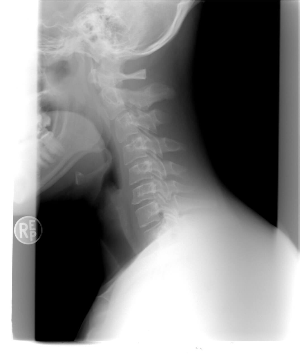

평소에 거북목 증상이 있다면 뒷목이 땡기는 두통이 발생할 가능성이 높습니다. 거북목 증후군이란 옆에서 보았을 때 C자 형태의 커브를 유지해야 하는 경추(목뼈)가 일자로 변형된 것을 말합니다.

이처럼 잘못된 자세로 인해 변형된 경추는 머리의 무게를 제대로 지탱하지 못하게 되어 뒷목이 뻐근하고 당기는 증상을 유발하게 됩니다. 이 때문에 뒷목과 어깨 결림, 심한 경우에는 편두통까지 발생할 수 있으며, 경추 추간판 탈출증으로 발전할 가능성이 높으므로 각별한 주의가 필요합니다.